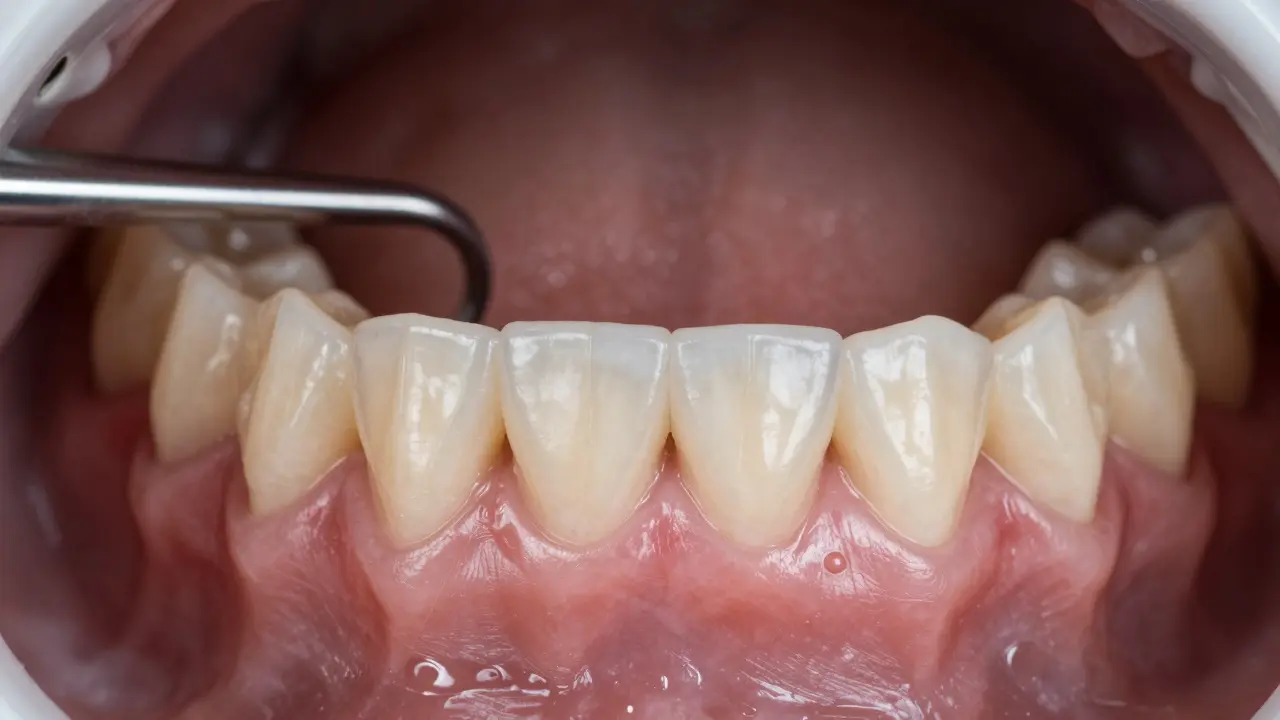

Zubní lékař odstraňuje zubní kámen pod dásní ultrazvukovým nástrojem.

Jak se zubní kámen pod dásní odstraní?

Tady je klíčové: neodstraníš ho doma. Žádná domácí metoda, žádná ústní voda, žádný speciální kartáček to nezvládne. Kámen pod dásní se odstraní jen u zubního lékaře, pomocí speciálních nástrojů.

Postup se jmenuje skalování a korekce povrchu kořene. To zní složitě, ale je to jednoduché:

1. Zubní lékař nejprve použije ultrazvukový nástroj, který rozpadá kámen na drobné částice - bez bolesti.

2. Poté použije ruční nástroje, které odstraní zbytky kamenů pod dásní.

3. Nakonec vyhladí povrch kořene zubu, aby se plak nemohl snadno znovu usadit.

Proces trvá obvykle 30-60 minut. Někdy se dělá ve dvou návštěvách, pokud máš kámen na více zubech. Můžeš cítit lehký tlak nebo pískání, ale nebolest. Pokud máš citlivé dásně, lékař ti může aplikovat lokální anestézii.